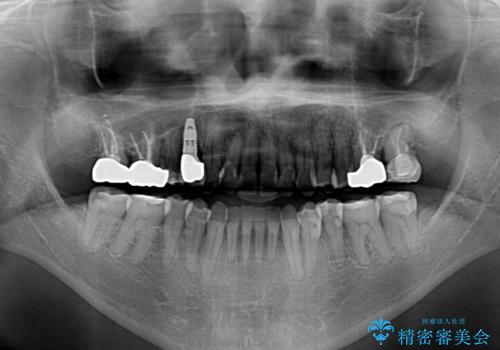

下顎骨の左右のずれがあり、下顎全体が前方に出ている状態であったので、無理をせずにワイヤー装置にて矯正治療を行うこととしました。

クロスバイト改善には難儀しましたが、咬みやすく、笑ったときに清潔感ある口元に仕上げることができました。